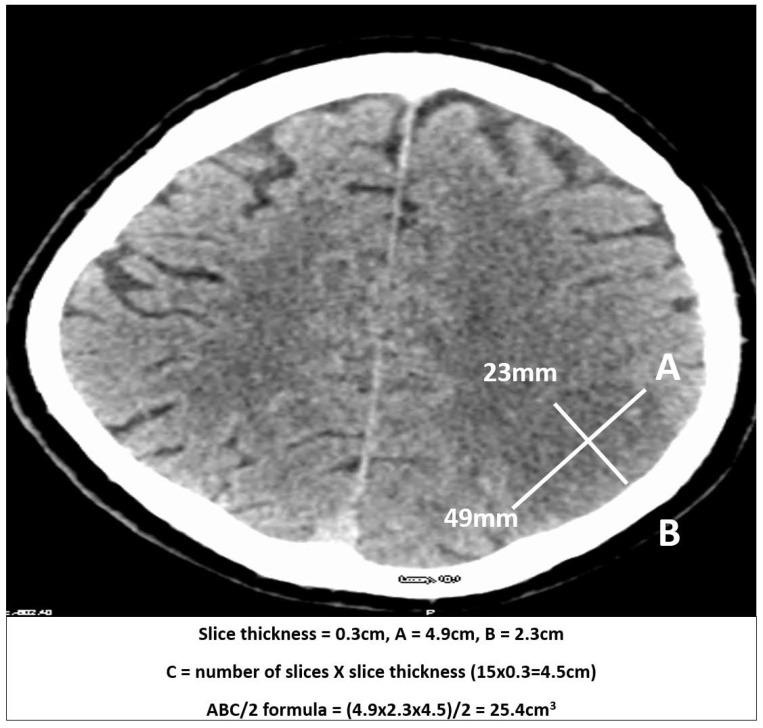

METHODS

Infarct volume was measured from NCCT in stroke patients recruited ≤12 h of symptoms onset and at 24 h using the ABC/2 method. Automated ischaemic volume measurements were carried out using e-ASPECTS software. Measurements using ABC/2 were compared with e-ASPECTS to assess volume differences and reliability using Lin's concordance correlation coefficient.

方法

对症状发作≤12小时及24小时时入组的卒中患者,利用ABC/2方法从非增强CT测量梗死体积。使用电子ASPECTS软件进行自动缺血体积测量。将ABC/2测量结果与电子ASPECTS进行比较,以使用林氏一致性相关系数评估体积差异和可靠性。